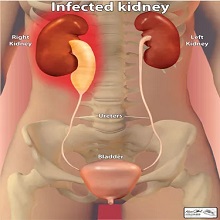

Пијелонефртитис представља запаљење ткива бубрега које траје (бубрежне карлице, чашица и каналића). По дужини трајања дели се на акутни и хронични. |

| Бубрези су парни органи, који представљају централни део уринарног система. Смештени су у ретроперитонеалном простору на задњем зиду абдомена, и налазе се са обе стране кичменог стуба. Десни бубрег, потиснут јетром, постављен је мало ниже у односу на леви. |